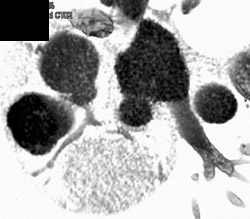

Diagnosis

Nice Femoral Arteries